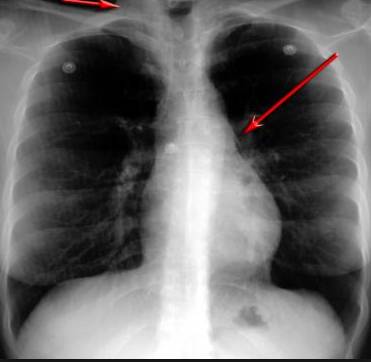

醫(yī)學(xué)掃描儀